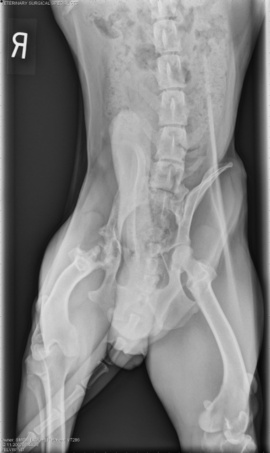

Trooper’s right hip was a disaster, as you can see from this X-ray. (His right hip is on the left side of this image as you look at it … you may need to click on the image to enlarge it.) Not only did he have a broken pelvis at one point, but the head of his femur — the "ball" that goes in the hip socket — was obliterated:

Joe said Trooper’s hip damage was from trauma of some sort … but what we don’t know. This poor dog has suffered from a birth defect at the front end and from trauma at the back end.